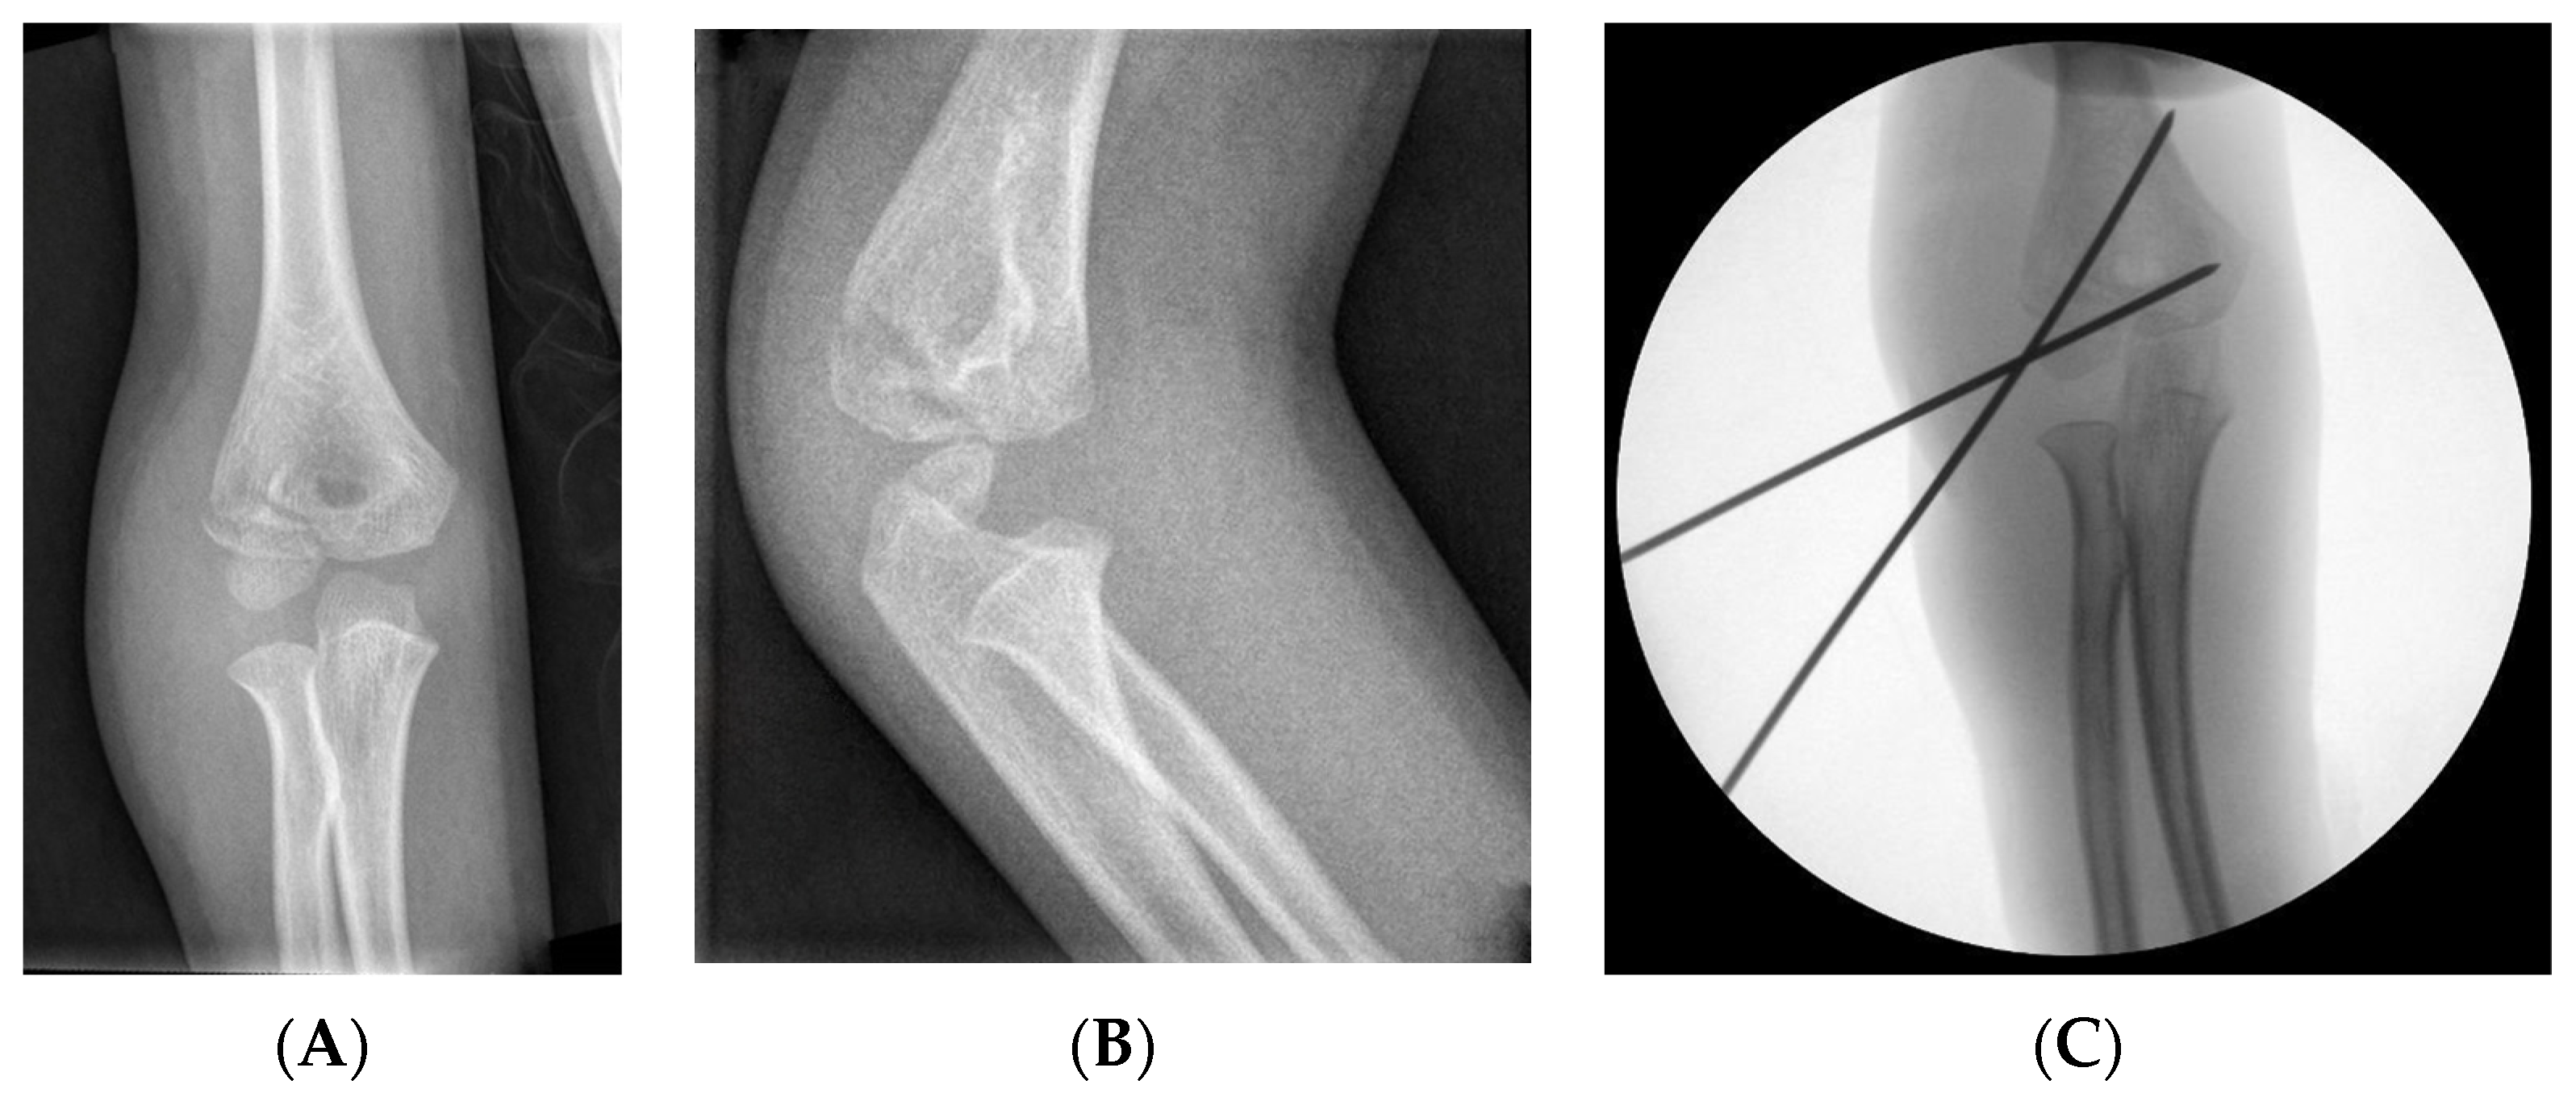

3.2.4. Fixation: Kirschner Wires

This is the fixation method preferred by most authors, using two or three KWs in a parallel or divergent position and passing through the contralateral cortex without crossing at the fracture site [4,6,31,36,39,40] (Figure 3). Depending on the fracture pattern, a KW parallel to the joint and/or a KW on the medial side can be used. In the case of open reductions, they must be inserted posteriorly to the incision [35].

Figure 3.

LHC fracture with 2 mm displacement. (A) AP view. (B) Internal oblique view. (C) Treatment with KWs, AP view.

KWs can be placed percutaneously, which simplifies removal [31,33,36], or subcutaneously [6], and they are usually removed after 4–6 weeks. However, shorter periods of 2–3 weeks have also been reported to provide good results [41].